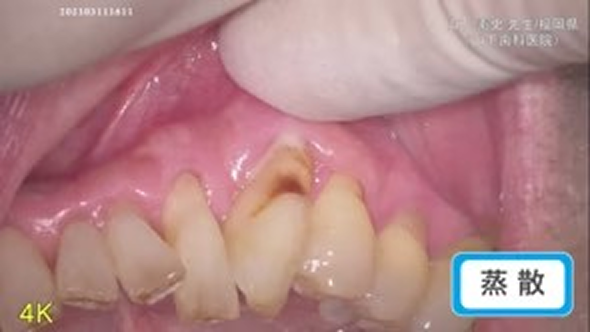

蒸散

臨床例:炭酸ガスレーザーPRO-X(最大出力15W)を使用した先生の臨床例です。